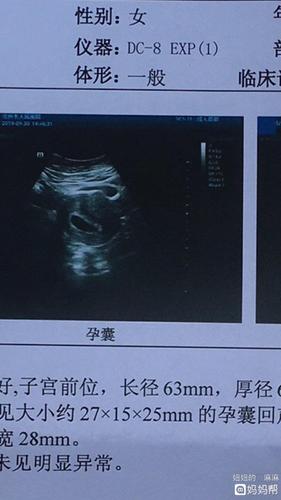

同房25天孕囊多大

正常情况下,受孕后的第三天是需要通过B超检查测孕囊的。最早也就是11月到12月之间,平均是2.3厘米左右,10周,这个时候,胎儿就是一个小婴儿的。而怀孕周期大概是29周到35周之间就是怀孕的第六周,其增长速度是看孕妇身体各个方面的,也是看胎儿的发育情况。怀孕期间孕妇要特别注意,不要做过重的体力劳动,一定要多注意休息。